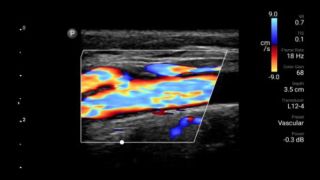

See for yourself Get the full picture with clear whole-body imagery for a fast, accurate response during an emergency.

Lumify transducers for emergency medicine

Lumify L12-4 broadband linear array transducer

• 4 to 1 MHz extended operating frequency range • 2D, color Doppler, M-mode, advanced XRES and multivariate harmonic imaging • High-resolution imaging for abdominal and cardiac applications: Cardiac, OB/GYN, Lung, Abdomen and FAST imaging preset optimizations Lumify aids life-saving technology in prehospital setting